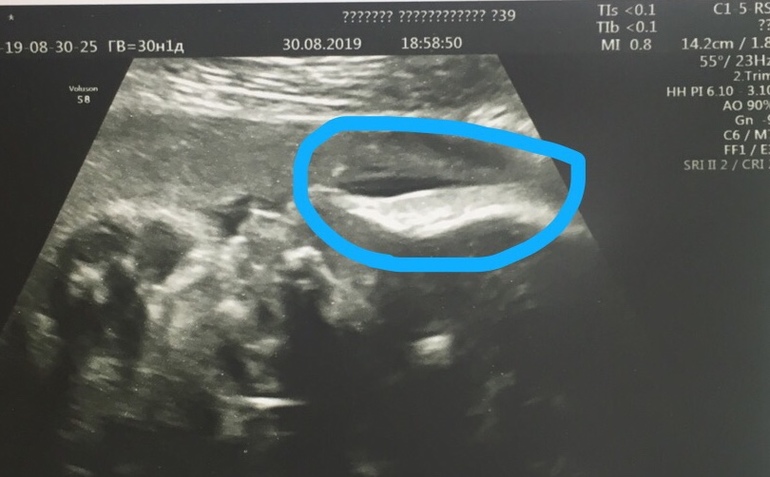

Вопросы про УЗИ, обследования и анализы: что, где, как, когда?Девочки! помогите пожалуйста разобраться что это такое на снимке вокруг головы, какая то плёночка. Или это и есть пузырь с околоплодными водами? Это профиль, носик и лоб